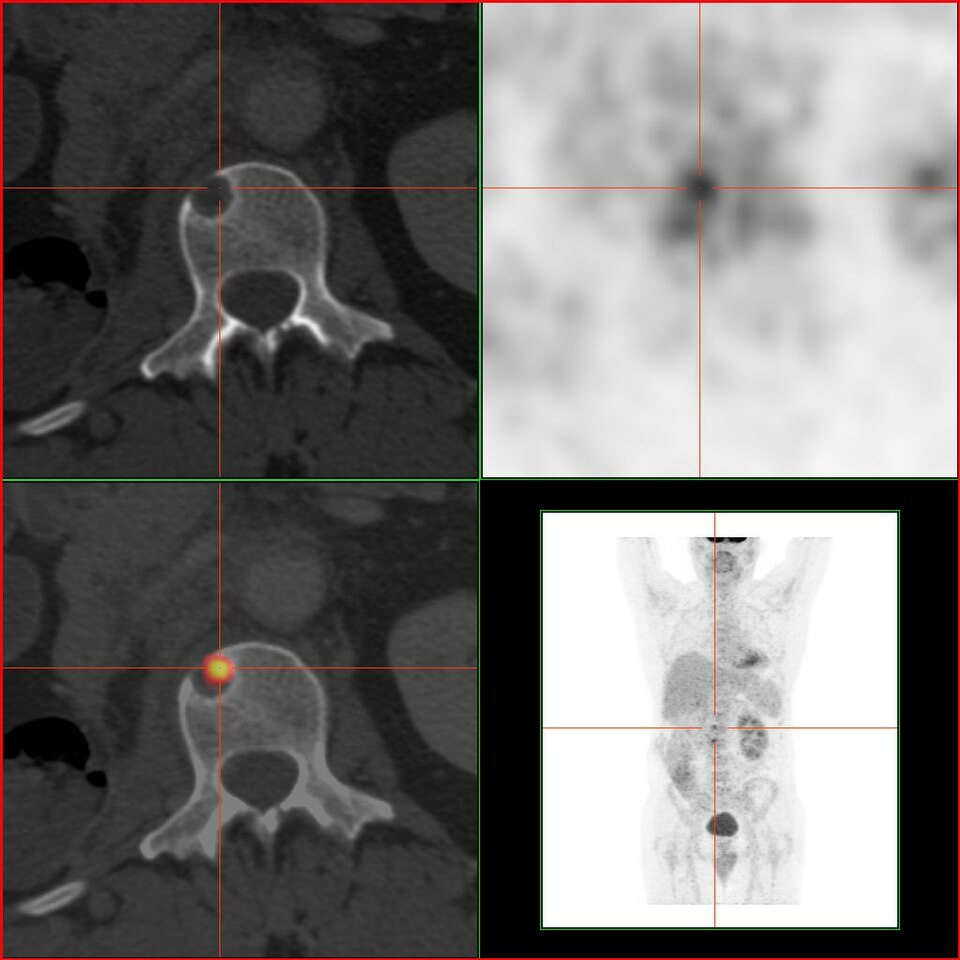

Whole-body PET/CT phantom with FDG-avid lesions in lung, liver, and lymph nodes for oncologic staging